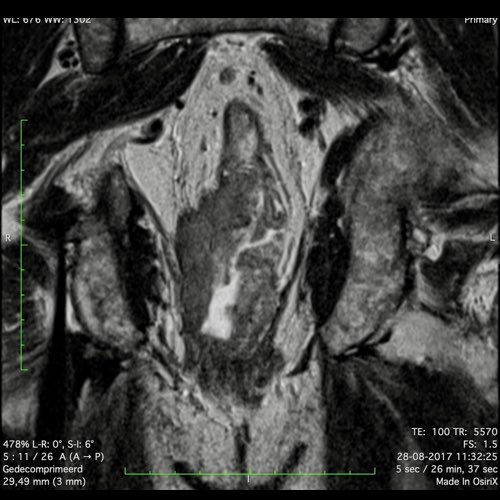

Hình ảnh

Các hình ảnh được cung cấp cho thấy ung thư biểu mô tế bào nhẫn với tình trạng dày lan tỏa thành trực tràng, hình ảnh bia bắn điển hình, và sự xâm lấn mỡ mạc treo trực tràng.